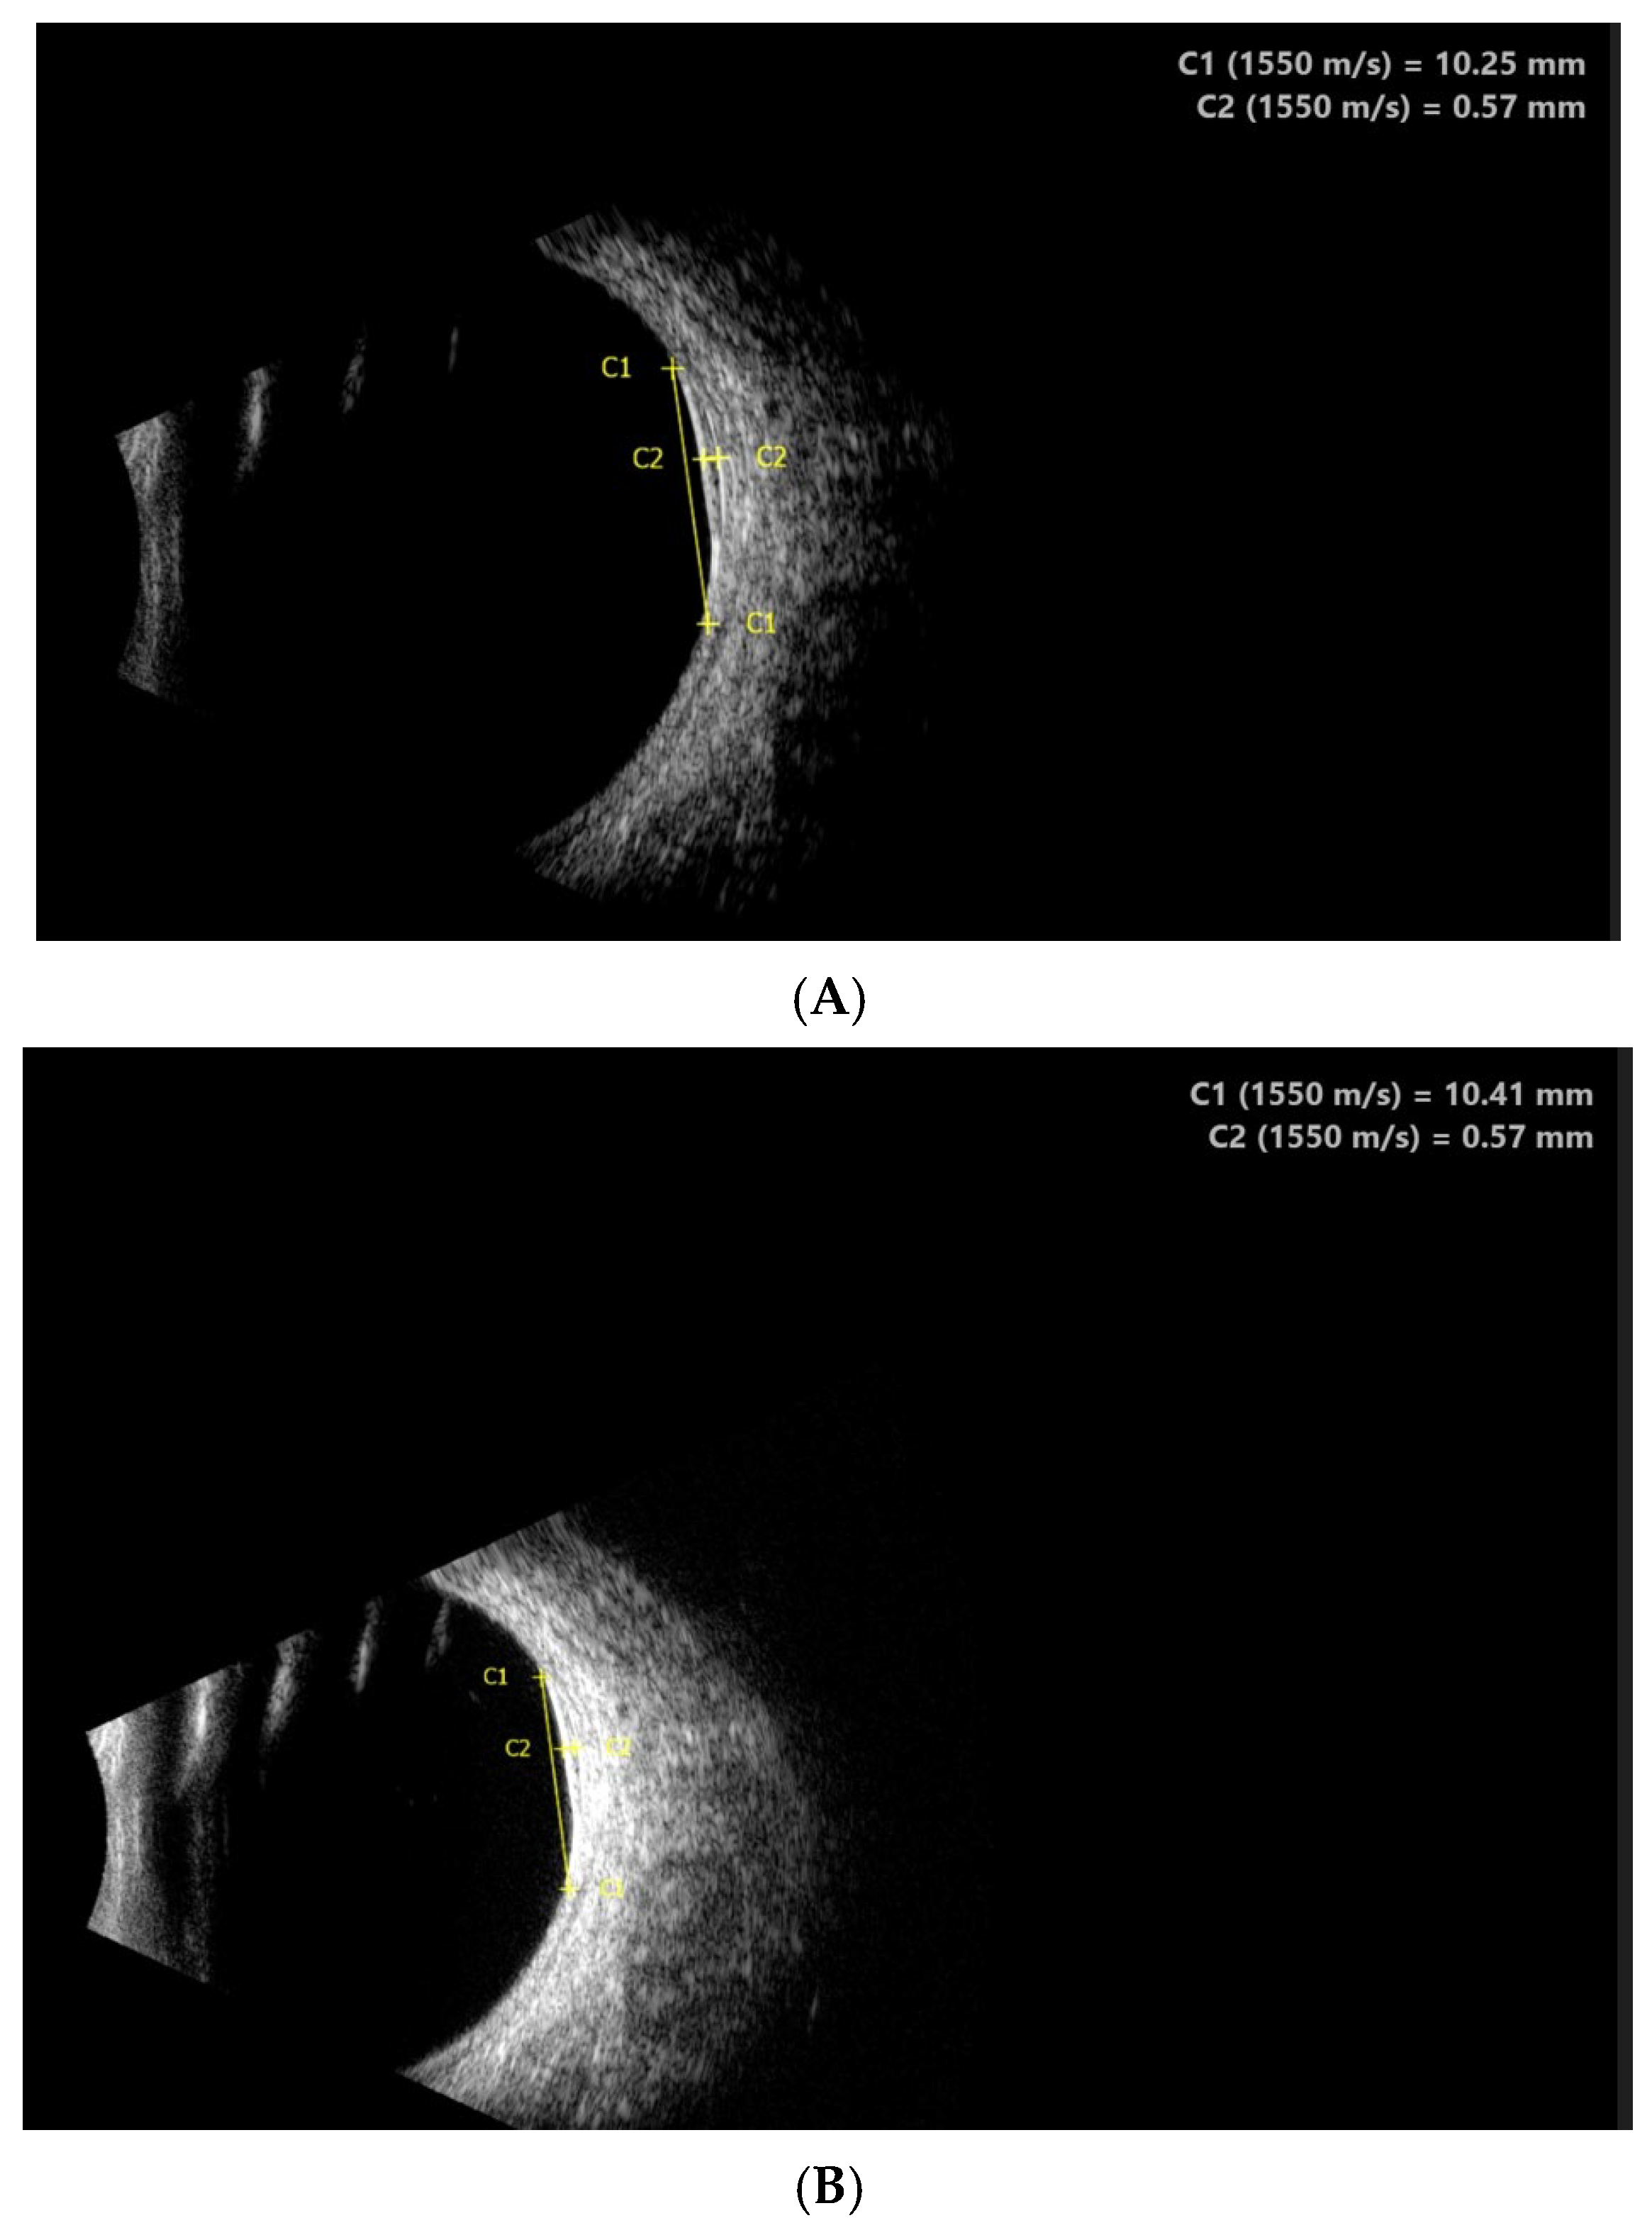

2.3. Diagnostic Assessment